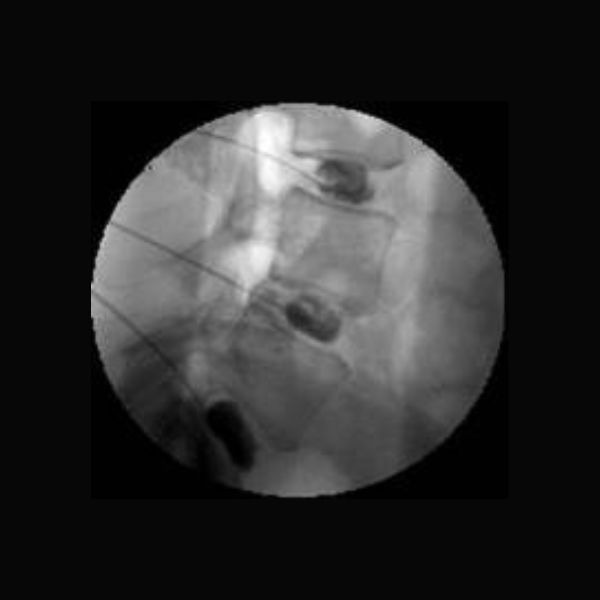

Η δισκογραφία εφαρμόζεται με τον ασθενή σε πρηνή θέση και υπό ακτινοσκοπικό έλεγχο. Ο ασθενής παραμένει ξυπνητός και συνεργάζεται με τον ιατρό. Μετά από προσεκτική αντισηψία του δέρματος και τοπική αναισθησία στο σημείο εισόδου ειδικής βελόνας, αυτή προωθείται μέσα στον πυρήνα του υπό εξέταση μεσοσπονδύλιου δίσκου, χωρίς να γνωρίζει ο ασθενής ποιος είναι αυτός.

Με ειδική συσκευή που συνδέεται με τη βελόνα, εγχύεται σκιαστικό και γίνεται μέτρηση του όγκου του  και της ενδοδισκιικής πίεσης και τα στοιχεία καταγράφονται αναλυτικά. Αν κατά την αύξηση της πίεσης εντός του δίσκου ο ίδιος ο ασθενής αναφέρει πόνο παρόμοιο με αυτόν που τον βασανίζει και ικανής έντασης (>7/11), τότε πιθανότατα ο συγκεκριμένος δίσκος είναι η αιτία του πόνου. Για να επιβεβαιωθεί αυτό το εύρημα, ακολουθεί δισκογραφία και δύο ακόμη δίσκων αναφοράς, για να γίνει σύγκριση με κάποιον πιθανόν υγιή δίσκο που δεν προκαλεί πόνο και εμφανίζει φυσιολογική καταγραφή πιέσεων και διάχυση του σκιαστικού εντός του πυρήνα.

Η επεμβατική εξέταση διαρκεί περίπου 30 λεπτά έως μια ώρα και στη συνέχεια ακολουθεί αξονική τομογραφία που εμφανίζει ακριβώς την κατανομή και διάχυση του σκιαστικού μέσα στο μεσοσπονδύλιο δίσκο. Με βάση την τελευταία εξέταση γίνεται κατάταξη της ενδοδισκικής εκφύλισης σύμφωνα με  την κλίμακα Dallas.